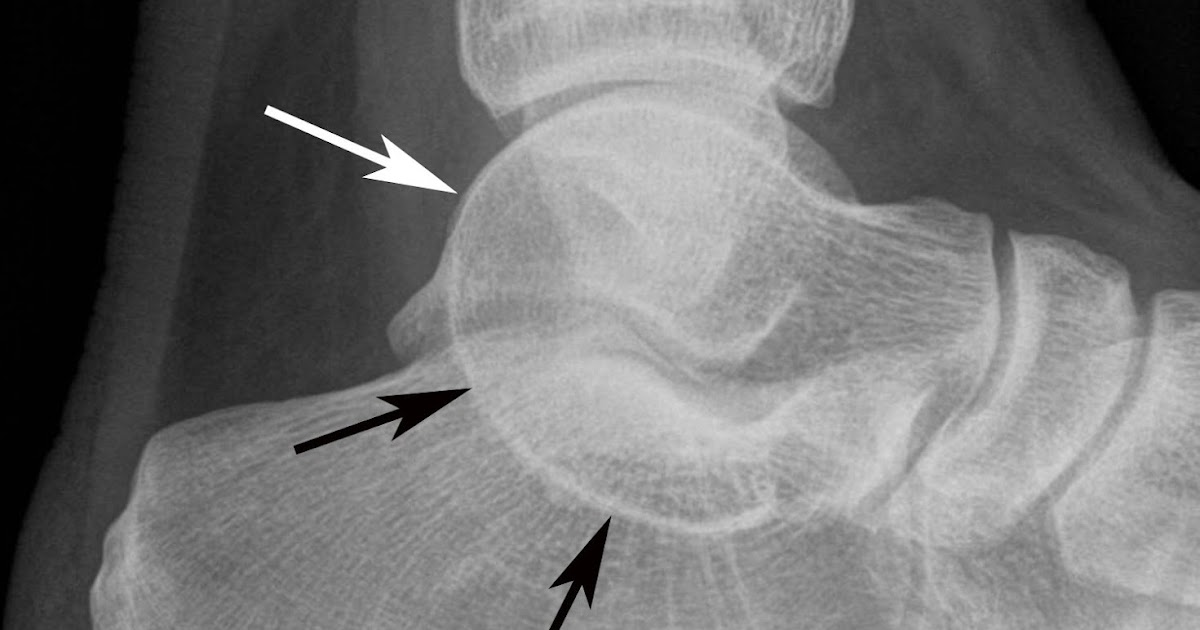

Tarsal Coalition Awareness: What Is A Tarsal Coalition?

Tarsal Coalition Awareness: What is a Tarsal Coalition? tarsalcoalitionawareness.blogspot.com

tarsal coalition